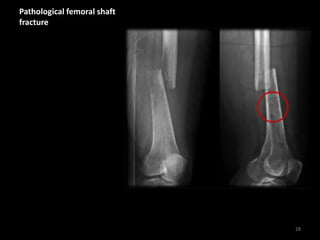

Pathological femoral shaft

fracture

28

Transverse fracture with

rotational displacement

and shortening

Patient with known

history of widespread

bone metastases - note

the abnormal bone

texture

Injury occurred after a

trivial fall

29